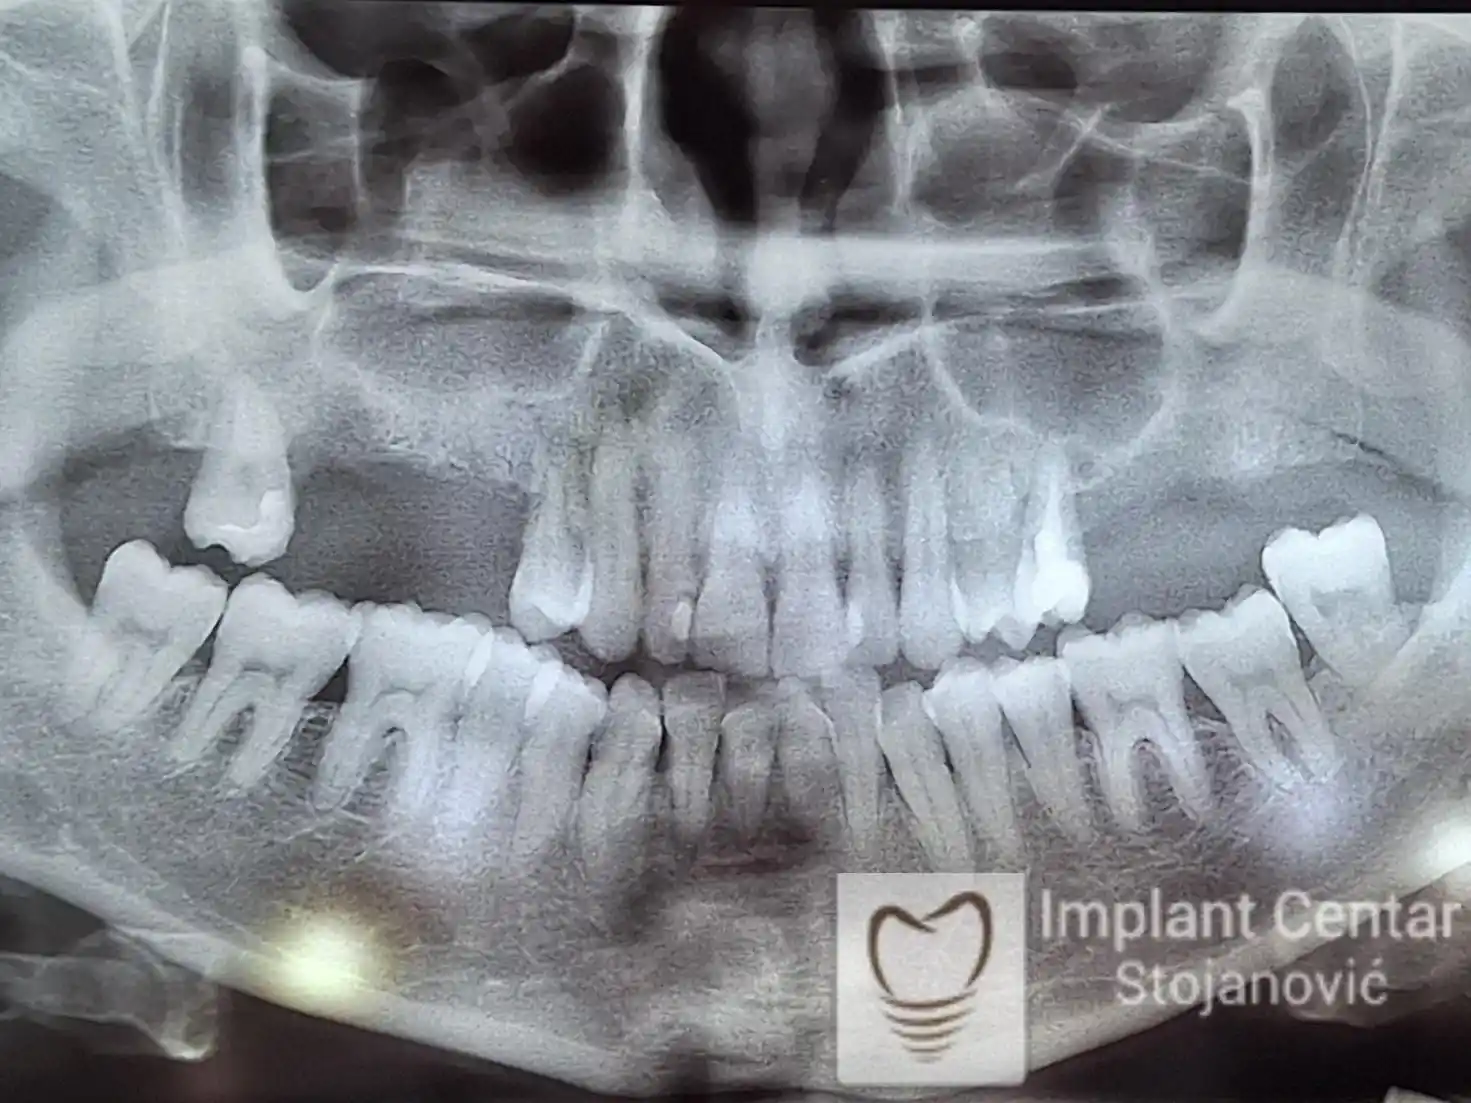

Pacijent kod koga je, zbog uznapredovale parodontopatije, bilo indikovano vađenje svih preostalih zuba.

Na slici 1. i slici 2. prikazan je izgled pacijenta pre početka terapije – klinički i rendgenološki.

Nakon vađenja zuba, ugrađeni su implantati. Na slici 3 prikazan je ortopan snimak sa ugrđenim implantatima. Tokom perioda osteointegracije, pacijent je bio zbrinut fiksnim privremenim krunicama na implantatima, koje su izrađene samo dva dana nakon hirurške intervencije.